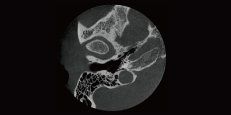

Airway Measurement

Automatically calculate the volume and the narrowest area of the airway in the form of chromatographic visualization.